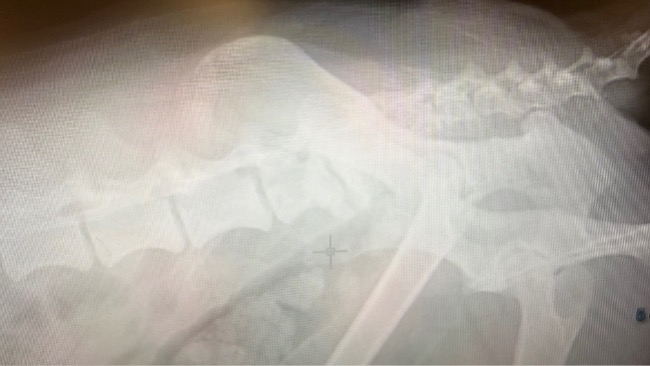

Aby dać mu szansę na życie bez bólu, musimy wykonać pełne badania krwi, USG, RTG oraz echo serca. To dopiero początek, bo wraz z wynikami pojawią się kolejne decyzje, leczenie, leki, odpowiednia dieta i dalsza opieka. Koszty będą wysokie, ale nie mamy wyboru. Benito przez całe życie nie miał nic. Teraz musi dostać wszystko, czego przez lata był pozbawiony.

Przed Benito ogrom badań, prawdopodobnie pierwszych w jego życiu. Pełna diagnostyka krwi, USG jamy brzusznej, RTG oraz echo serca. Do tego konsultacje specjalistyczne, leczenie, suplementacja i dalsza opieka.